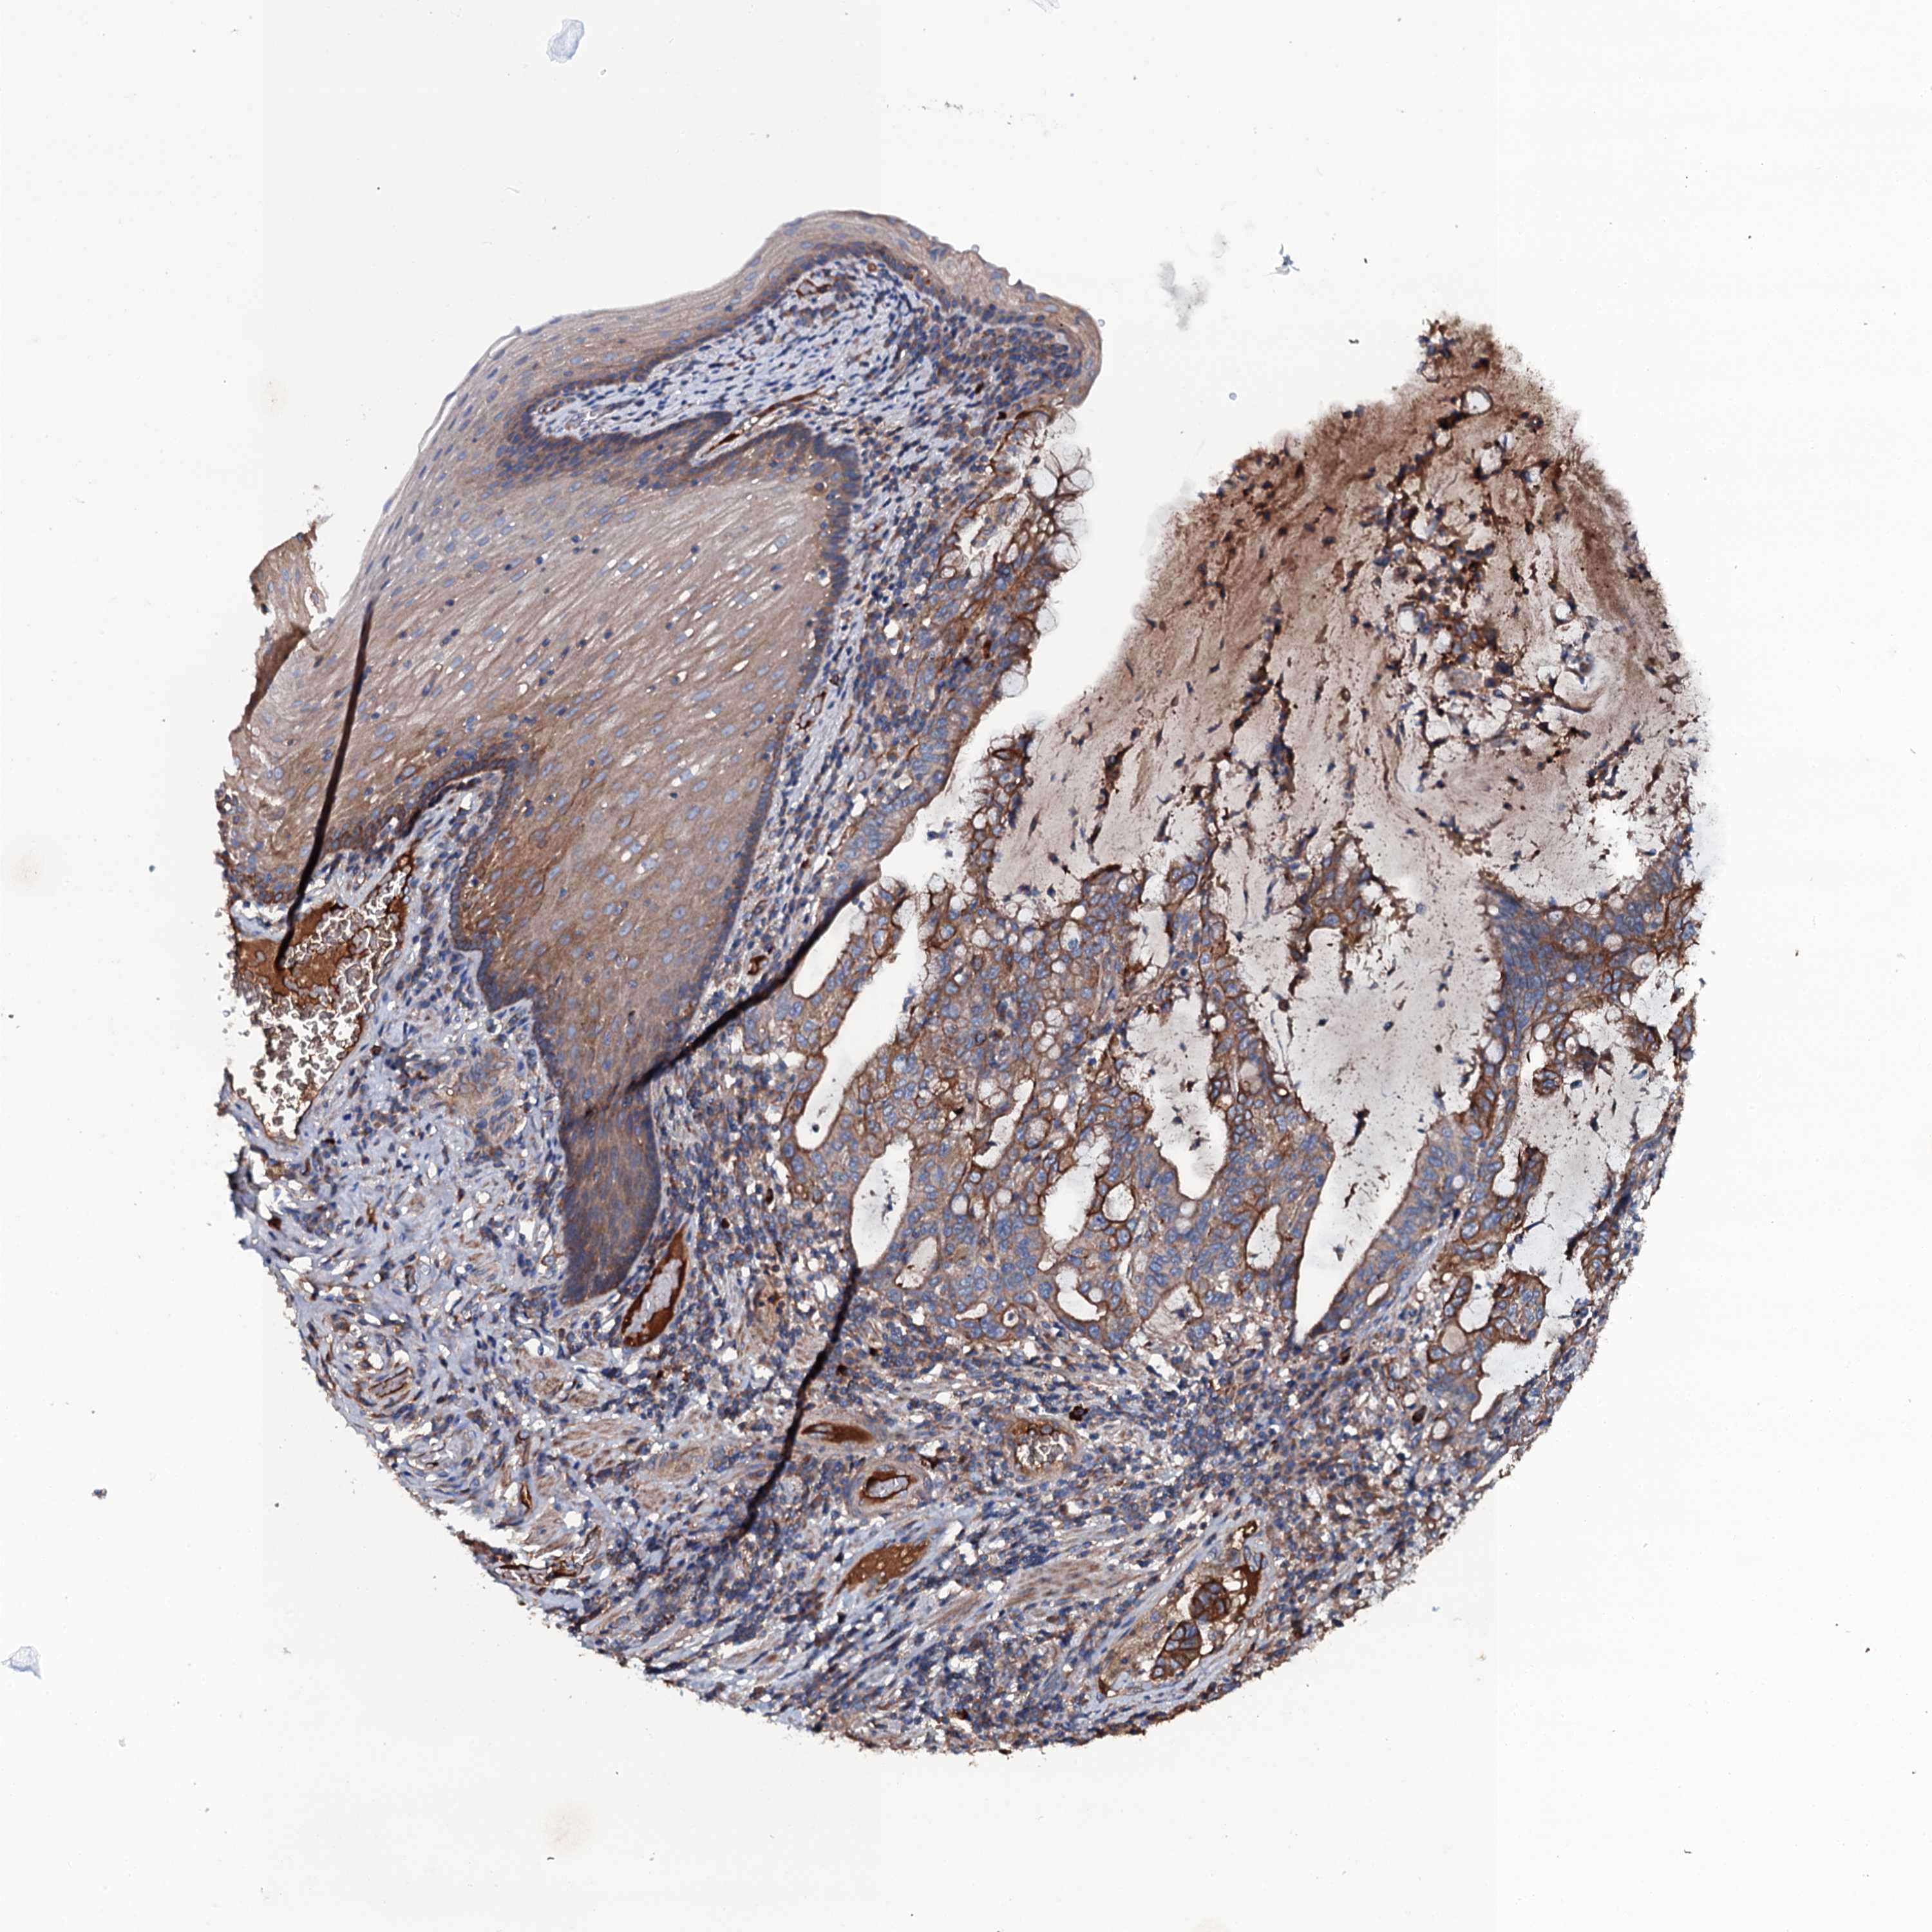

STOMACH CANCER - Protein expressioni

A mouse-over function shows sample information and annotation data. Click on an image to view it in a full screen mode. Samples can be filtered based on level of antibody staining by selecting one or several of the following categories: high, medium, low and not detected. The assay and annotation is described here.

Note that samples used for immunohistochemistry by the Human Protein Atlas do not correspond to samples in the TCGA dataset.

Antibody stainingi

Antibody staining in the annotated cell types in the current human tissue is reported as not detected, low, medium, or high, based on conventional immunohistochemistry profiling in selected tissues. This score is based on the combination of the staining intensity and fraction of stained cells.

Each image is clickable and will lead to virtual microscopy that enables deeper exploration of all samples and also displays staining intensity scores, fraction scores and subcellular localization as well as patient and tissue information for each sample.

Antibody HPA020873

Antibody HPA040413

Staining

High

Medium

Low

Not detected

Intensity

Strong

Moderate

Weak

Negative

Quantity

>75%

75%-25%

<25%

None

Location

Nuclear

Cytoplasmic/membranous

Cytoplasmic/membranous,nuclear

Adenocarcinoma, NOS

Adenocarcinoma, High grade